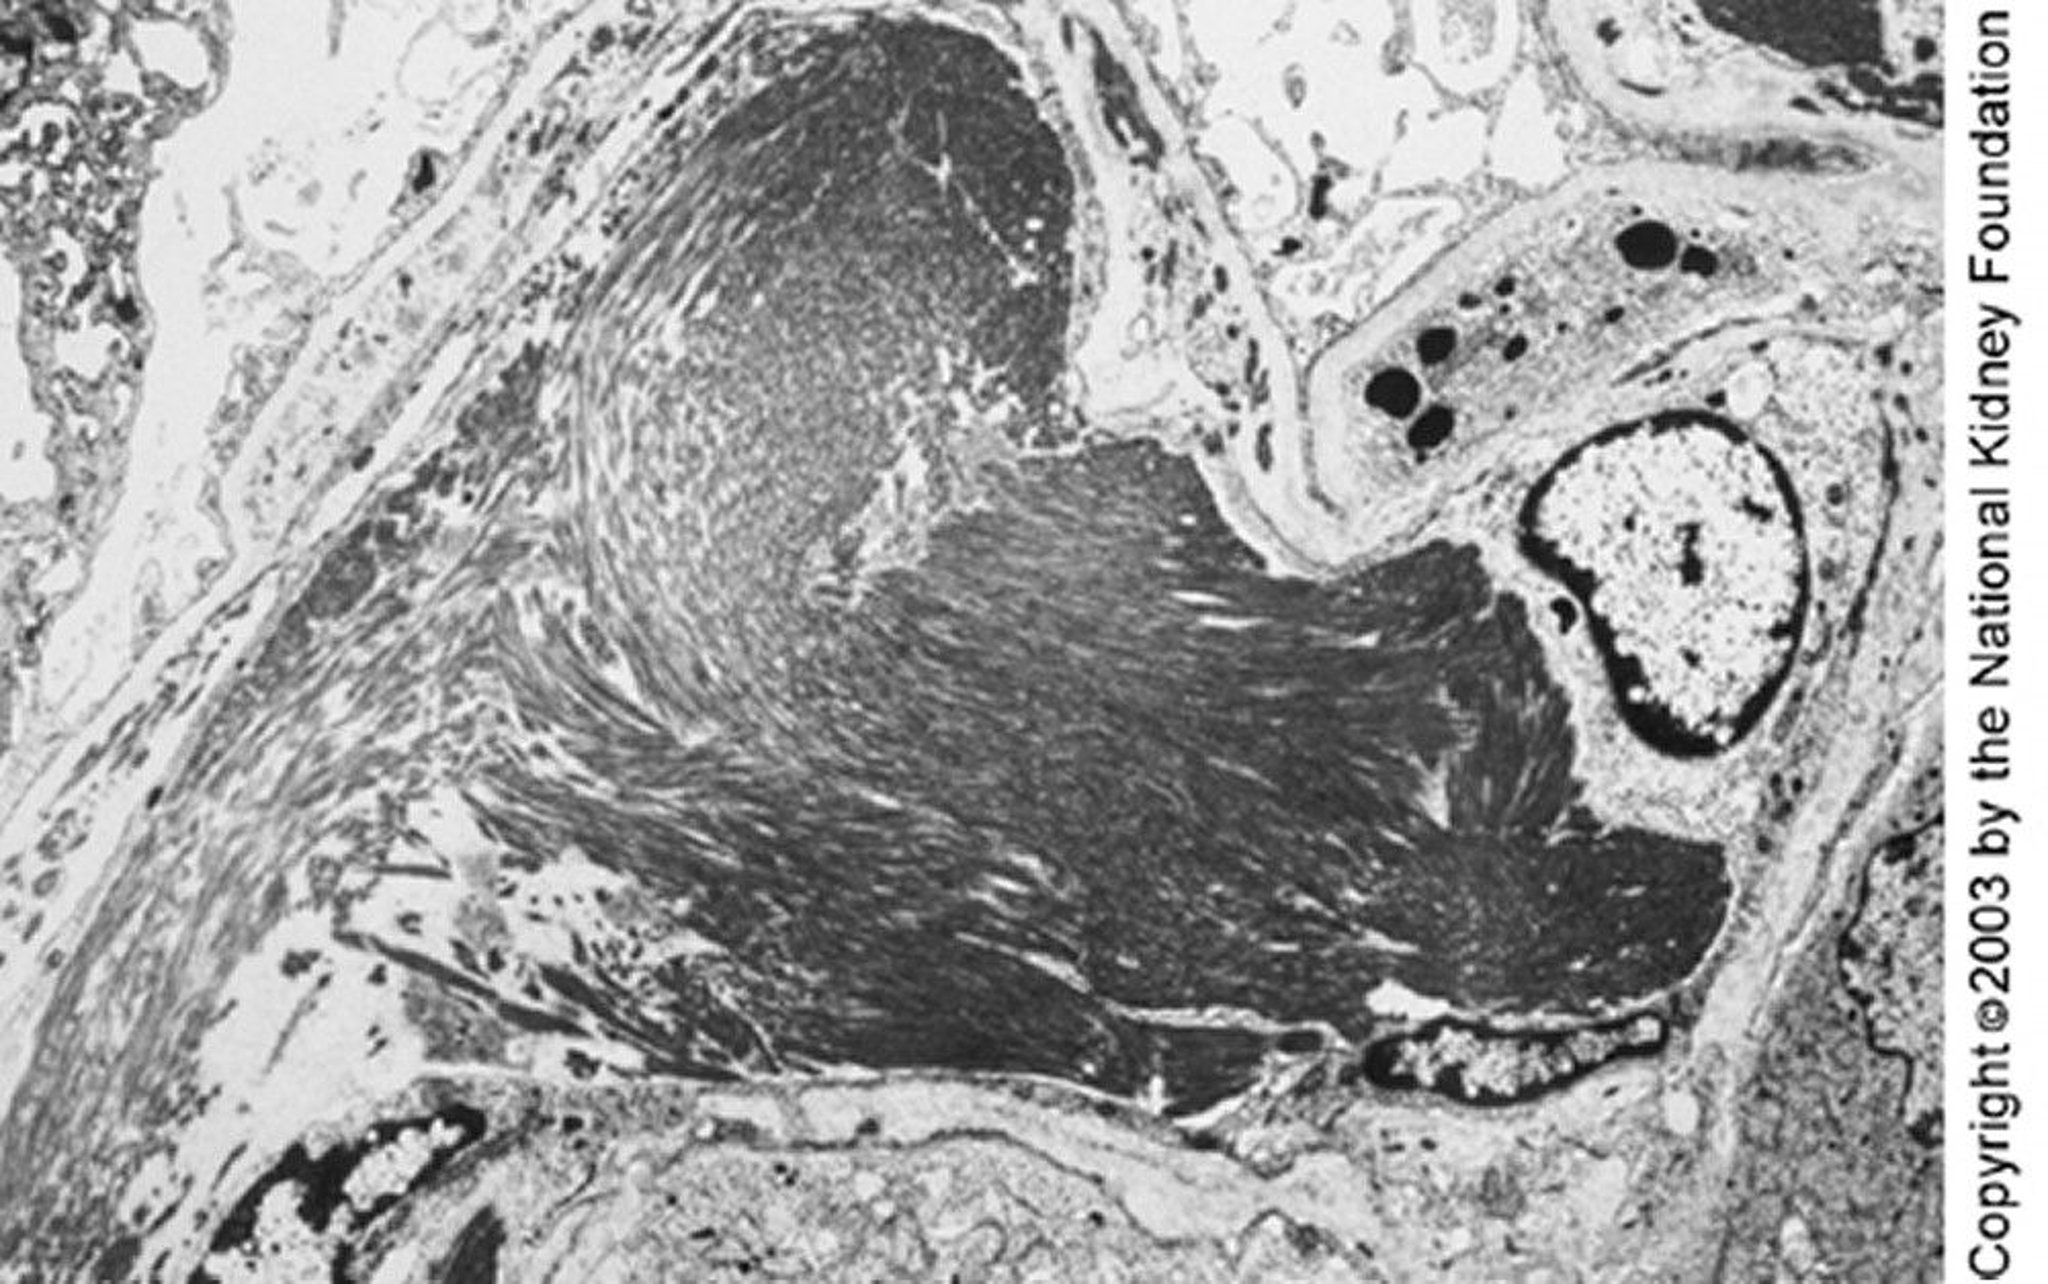

Immunotactoid Glomerulopathy

Large microtubules (close to 50 nm in diameter) organized in parallel arrays can be seen on transmission electron microscopy. The parallel deposits and microtubular structure may distinguish immunotactoid from fibrillary glomerulopathy (×4000).

Image provided by Agnes Fogo, MD, and the American Journal of Kidney Diseases' Atlas of Renal Pathology (see www.ajkd.org).